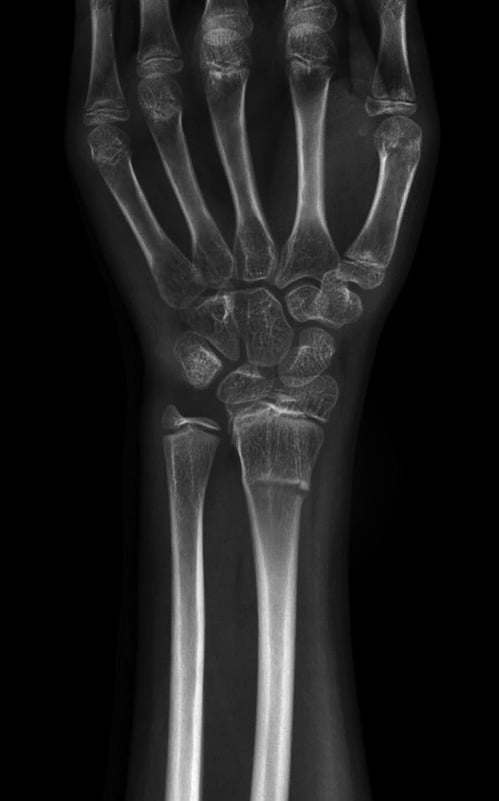

Fluoroscopic hand and wrist imaging allows our team members to see the structures and movements of the hand and wrist in real-time. It involves the use of a fluoroscope, a specialized imaging machine that captures continuous images, like an X-ray “movie” of the hand and wrist.

During a real-time fluoroscopic hand and wrist imaging procedure, the patient's hand or wrist is positioned under the fluoroscope to produce live images of the hand or wrist. These images are displayed on a monitor so your provider can observe the movement of bones, joints, and soft tissues in real-time.